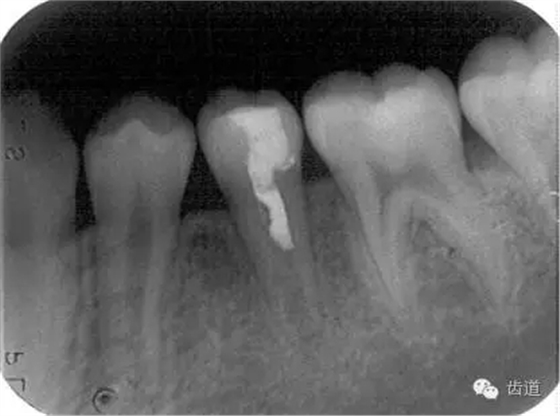

術(shù)后

術(shù)前

術(shù)后199日

術(shù)后1084日

牙根發(fā)育完成根尖閉鎖后, 應(yīng)及時(shí)改做根管充填術(shù)。由于此種牙齒根管粗大而壁薄,宜選用側(cè)壓充填法lateral condensation method或Ultrafil 3D三維注射式熱牙膠根管充填系統(tǒng)。